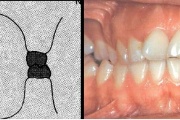

Sügav hambumus

ülemised eeshambad katavad täielikult alumisi